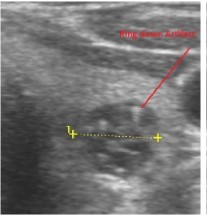

In our study many patients were found to have nodules look very much like PT adenoma, Figure 7 below. At least, 4 patients were subsequently confirmed to have parathyroid adenomas, Figure 8 and 2 patients underwent surgery

Despite the fact that nodular pathology was found to be very prevalent among our study population, it has been found difficult to differentiate between thyroid and parathyroid pathology using ultrasound alone. However, some characteristics of the parathyroid glands might suggest parathyroid pathology in the context of the clinical picture of secondary or tertiary hyperparathyroidism which is very prevalent in ESKD patients’ populations.

Figure 7.Thyroid nodule suspicious for Parathyroid adenoma due to its location

Figure 8.Nodule that proven to be a parathyroid adenoma, volume =5265 mm3

There are 4 parathyroid glands (2 superior, 2 inferior) imbedded within the thyroid gland. The parathyroid glands are bean-like shape and small (20-40 mg) 25. Sonographically, the parathyroid glands have the following features 25:

Hyperplastic glands: hypoechoic, volume <500 mm3.

Nodular glands: hypoechoic. Volume >500 mm3

Histologically, if the excised gland has volume <500 mm3 it is said to be hyperplastic and if the volume is more than 500 mm3 it is nodular hyperplasia in 80% of cases26. In secondary HPT, the increase in the volume of parathyroid glands is associated with increase in vascularity, as evident in Color Doppler imaging 27.